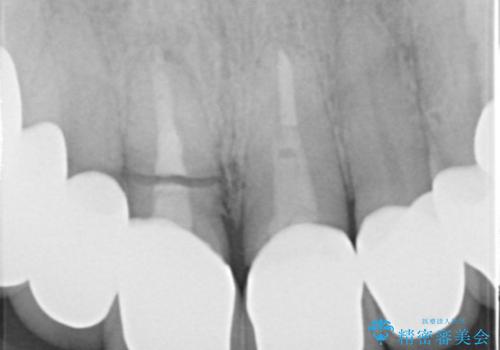

- 事故による外傷で前歯に歯根が真っ二つに折れてしまい、保存不可能となってしまった部分にインプラント治療を計画しました。

近年、インプラントの素材や手術法の研究が進み、保存不可能となった歯牙に対して抜歯してすぐインプラントを埋入し、さらに直後から仮歯がを入れ噛むことができる【抜歯即時埋入】【即時荷重】という技法が確立されました。